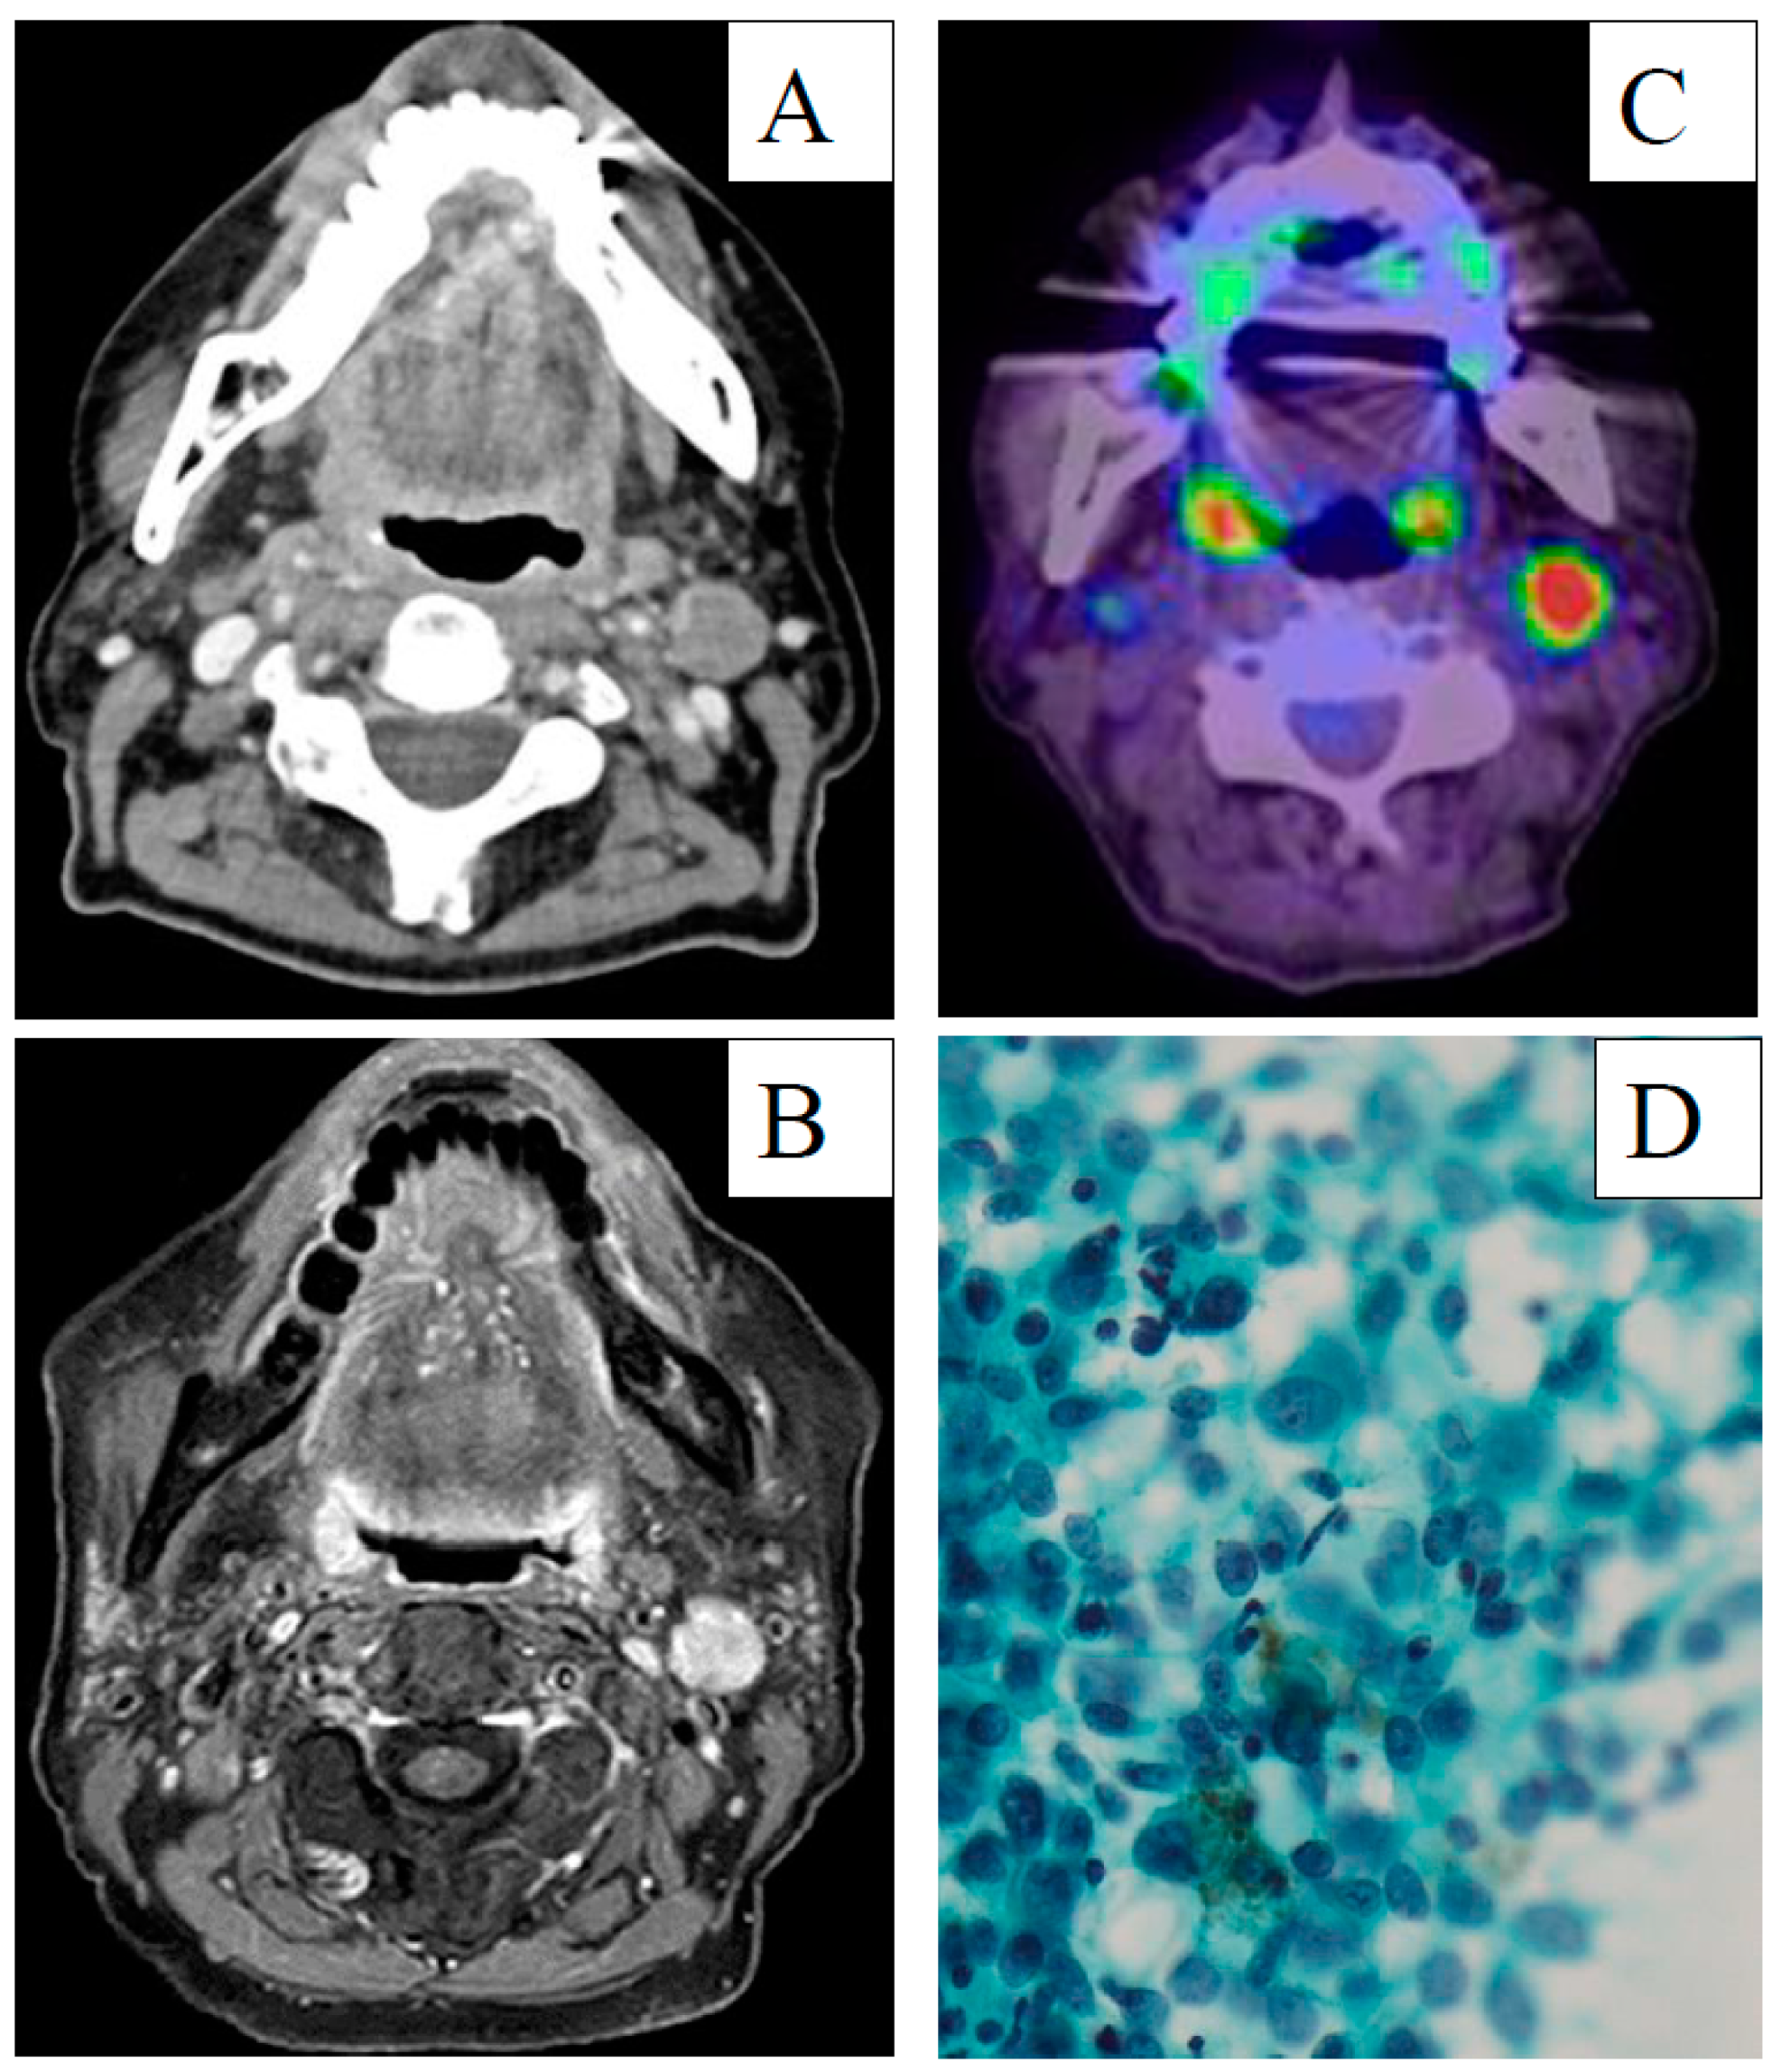

2. Case Report